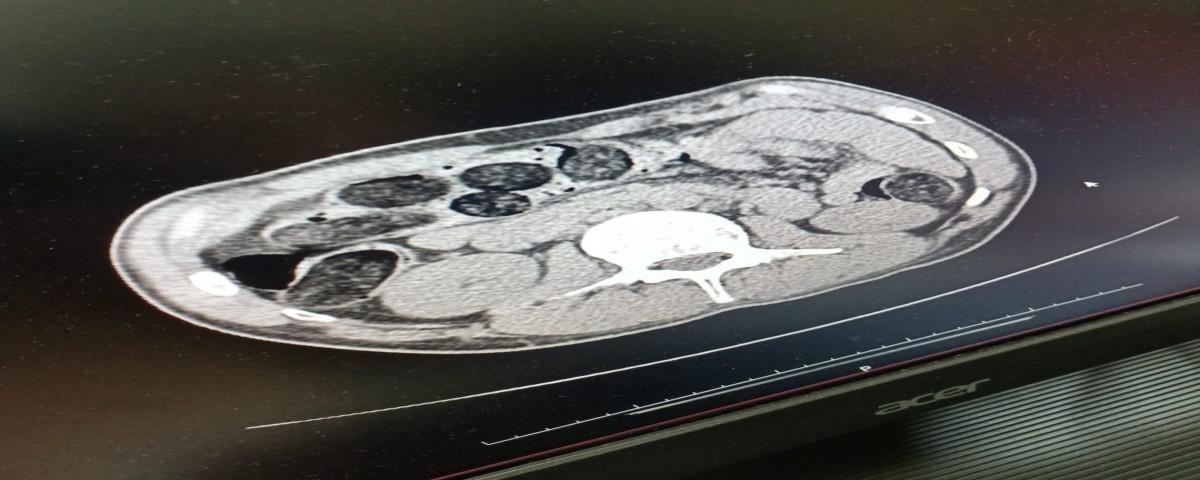

Bolu İl Emniyet Müdürlüğü Narkotik Suçlarla Mücadele Şube Müdürlüğü ekipleri tarafından yapılan operasyonda midesinde 542 gram Eroin maddesi tespit edilen 2 kişi adliyeye sevk edildi.

Edinilen bilgiye göre, Bolu İl Emniyet Müdürlüğü Narkotik Suçlarla Mücadele Şube Müdürlüğü ekipleri uyuşturucu madde bulundurma ve ticaretinin önlenmesine yönelik operasyon düzenledi. Düzenlenen operasyonda doğu illerinden batı illerine giden yolcu otobüsü içerisinde bulunan iki şahsın iç beden muayenesi sonucunda Şefik B. isimli şahsın midesinde, 48 parça kapsül halinde toplam ağırlığı 542 gram gelen Eroin  maddesi ele geçirildi. Yapılan operasyonda konu ile alakalı Aykut.T ile 2 farklı suçtan aranan ve 17 yıl 6 ay Hapis Cezası olan Şefik B. isimli şahıslar hakkında  Uyuşturucu Madde Ticareti  suçundan gözaltına alınarak emniyetteki işlemlerinin ardından adliyeye sevk edildi.